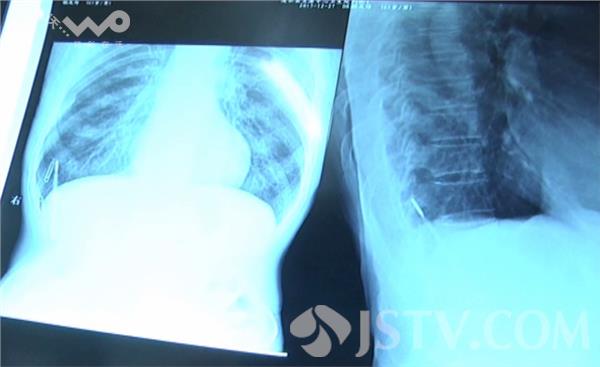

本来身体没有什么问题的嵇老汉听说这情况以后,陡然感觉不舒服,急忙找到了家里亲戚,涟水五港卫生院邵主任。邵主任在详细了解嵇老汉的病情以后决定就在五港医院给嵇老汉手术取异物。为确保万无一失院方从淮安请来一位专家主刀,手术非常成功顺利。当体温计从嵇老汉体内取出后,现场医护人员也十分震惊。

据五港医院的邵主任和贾医师介绍,嵇老汉体内的体温计存在于体内的腹肌与胸肌之间,十分危险,如果不是这次偶然发现,生活中一旦遇到外力,就很可能戳穿其他内脏,那样生命就很成问题,或者体温计破裂也就出事了。这次发现也算嵇老汉命大。记者在问及嵇老汉当年是在苏州的哪家医院做的手术,他自己也说不清楚,表示在外做工就跟着老板走,也不知道具体的地址只知道医院是在苏州。目前,嵇友传手术很顺利各方面一切正常,正在医院治疗中。